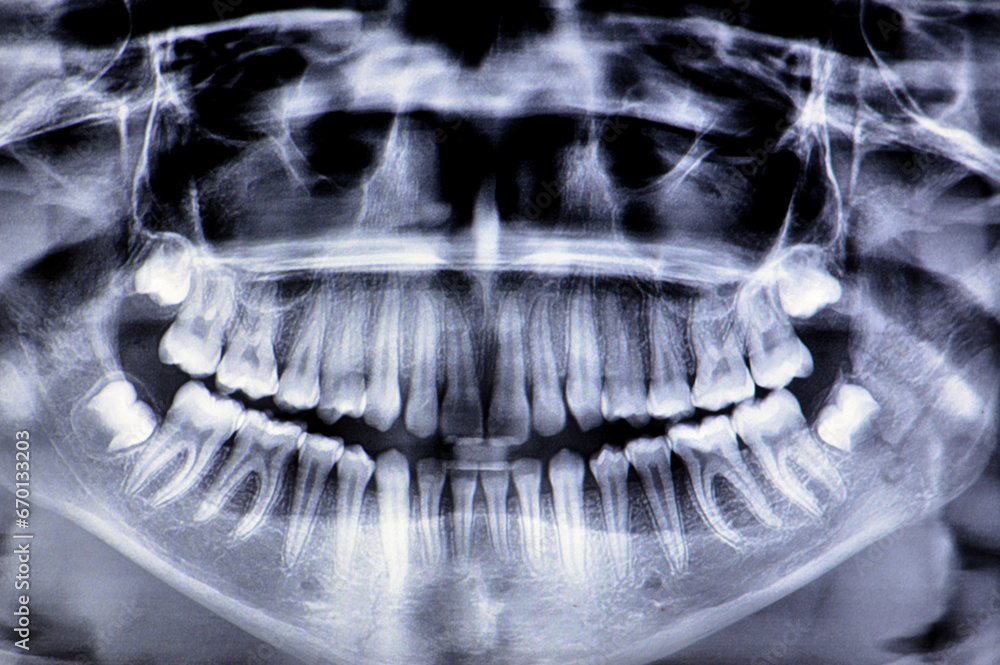

Panoramic radiograph is a scanning dental Xray of the upper jaw X Ray Of Jaw Bone how is bone loss in the jaw detected? in this review, we examine the advances and the difficulties of the diagnosis and the various treatment. rarely, jaw cancer may arise on its own as an osteosarcoma, a type of cancer that forms in the bone. Potential symptoms include swelling, pain, fever, and oral discharge. jaw bone. X Ray Of Jaw Bone.